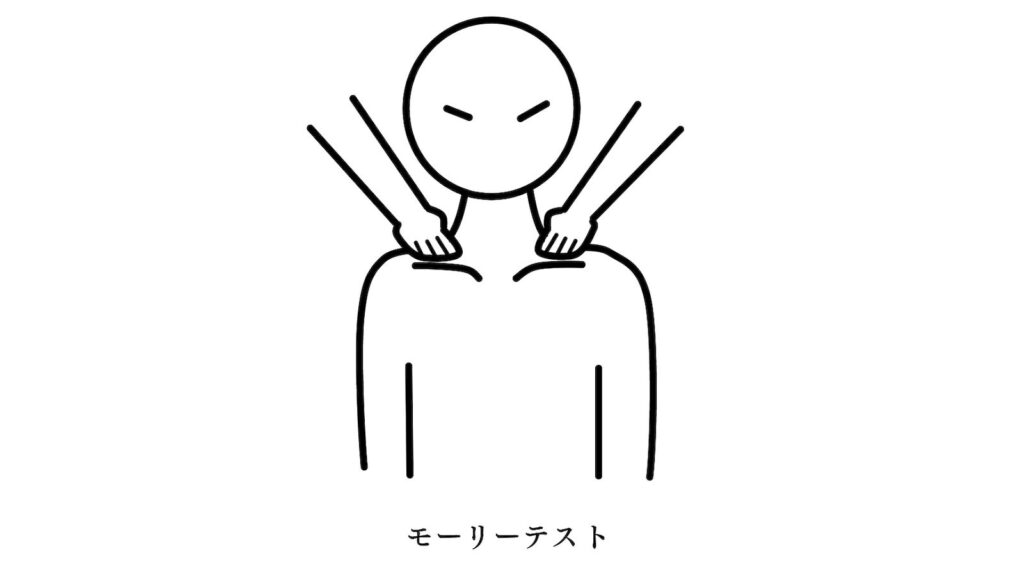

胸郭出口症候群の評価で用いるモーリーテストも陽性でした。

「胸郭出口症候群とは・・・?」

https://www.joa.or.jp/public/sick/condition/thoracic_outlet_syndrome.html

※日本整形外科学会より